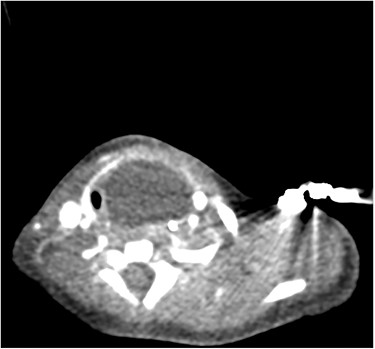

The patient underwent a computed tomography (CT) scan that illustrated a large left-sided supraglottic cyst (3.5 × 2.4 × 2.9 cm) extending from C3 to C7 with paratracheal extension (Figs 1–3). This was confirmed on microlaryngobronchoscopy (MLB) and the cyst was drained. The patient was managed postoperatively in the paediatric intensive care unit where she remained intubated. Extubation was unsuccessful, secondary to worsening stridor and increased work of breathing; a chest X-ray revealed a collapsed right lung. A second MLB was performed and thick bronchial secretions were found, as well as subglottic inflammation, in keeping with a diagnosis of tracheitis.